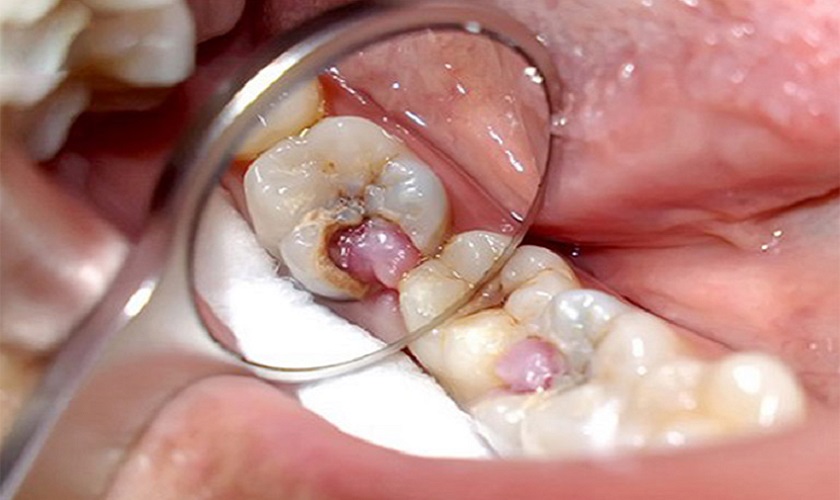

Một biến chứng nghiêm trọng hơn của bọc răng sứ là viêm tủy, một tình trạng đau đớn và có thể làm hỏng cả răng gốc. Viêm tủy xảy ra khi mão sứ không được lắp đặt chính xác, dẫn đến sự xâm nhập của vi khuẩn vào tủy răng. Điều này không chỉ gây đau đớn mà còn có thể làm giảm tuổi thọ của răng gốc, đòi hỏi phải điều trị tủy hoặc thậm chí là nhổ răng.